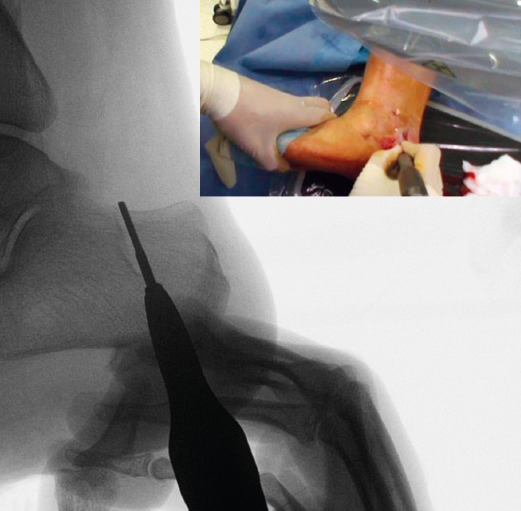

Figura 5. Imagen fluoroscópica del trazo dorsal de la osteotomía y su correspondencia en cirugía.

La fresa se coloca en línea con el trazo de osteotomía dibujado en la piel, primero el dorsal y después el plantar (Figuras 5 y 6), y va cortando la pared lateral y el hueso esponjoso del calcáneo y progresando paulatinamente hasta alcanzar la segunda cortical y cortarla cuidadosamente. Se recomienda no superar en 6.000 rpm la velocidad de la fresa para evitar la osteonecrosis térmica. A pesar de que el procedimiento se realiza sin isquemia para que la sangre refrigere el calor de la fresa, se recomienda que el ayudante aporte suero salino para contribuir a tal efecto.

Figura 6. Imagen fluoroscópica del trazo plantar de la osteotomía y su correspondencia en cirugía.